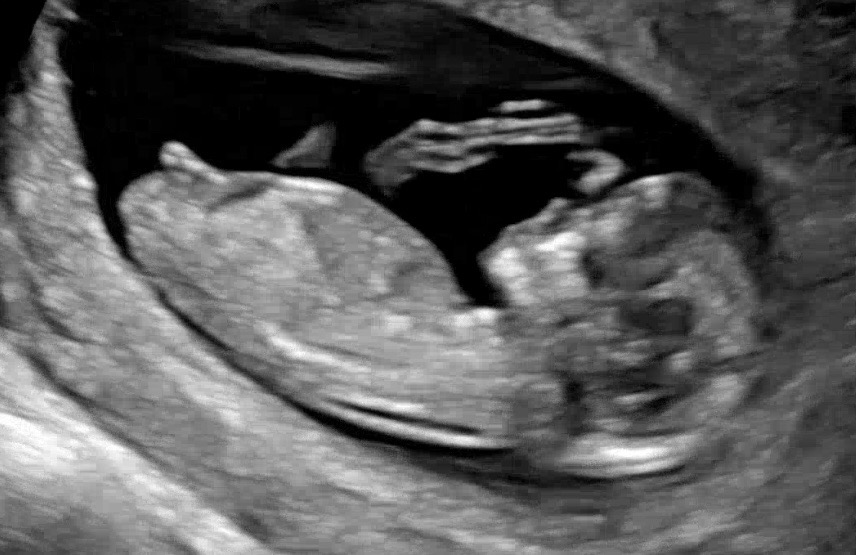

12주 1일차 각도법 고수님들 참견 마구 부탁드려요~~~

12주 1일차 각도법 고수님들 참견 마구 부탁드려요~~~ 감사합니당~~~

각도가 평행에 가까운거 보니 딸일거 같아요!

딸에 한표요!

끝이 갈라진게 딸같아요!

딸일수있지만 반전가능성있어요